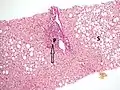

The gold standard for diagnosis of cirrhosis is a liver biopsy. This is usually carried out as a fine-needle approach, through the skin (percutaneous), or internal jugular vein (transjugular).[77] Endoscopic ultrasound-guided liver biopsy (EUS), using the percutaneous or transjugular route, has become a good alternative to use.[78][77] EUS can target liver areas that are widely separated,[79] and can deliver bi-lobar biopsies.[78] A biopsy is not necessary if the clinical, laboratory, and radiologic data suggest cirrhosis. Furthermore, a small but significant risk of complications is associated with liver biopsy, and cirrhosis itself predisposes for complications caused by liver biopsy.[80]

Once the biopsy is obtained, a pathologist will study the sample. Cirrhosis is defined by its features on microscopy: (1) the presence of regenerating nodules of hepatocytes and (2) the presence of fibrosis, or the deposition of connective tissue between these nodules. The pattern of fibrosis seen can depend on the underlying insult that led to cirrhosis. Fibrosis can also proliferate even if the underlying process that caused it has resolved or ceased. The fibrosis in cirrhosis can lead to destruction of other normal tissues in the liver: including the sinusoids, the space of Disse, and other vascular structures, which leads to altered resistance to blood flow in the liver, and portal hypertension.[81]

As cirrhosis can be caused by many different entities which injure the liver in different ways, cause-specific abnormalities may be seen. For example, in chronic hepatitis B, there is infiltration of the liver parenchyma with lymphocytes.[81] In congestive hepatopathy there are erythrocytes and a greater amount of fibrosis in the tissue surrounding the hepatic veins.[83] In primary biliary cholangitis, there is fibrosis around the bile duct, the presence of granulomas and pooling of bile.[84] Lastly in alcoholic cirrhosis, there is infiltration of the liver with neutrophils.[81]